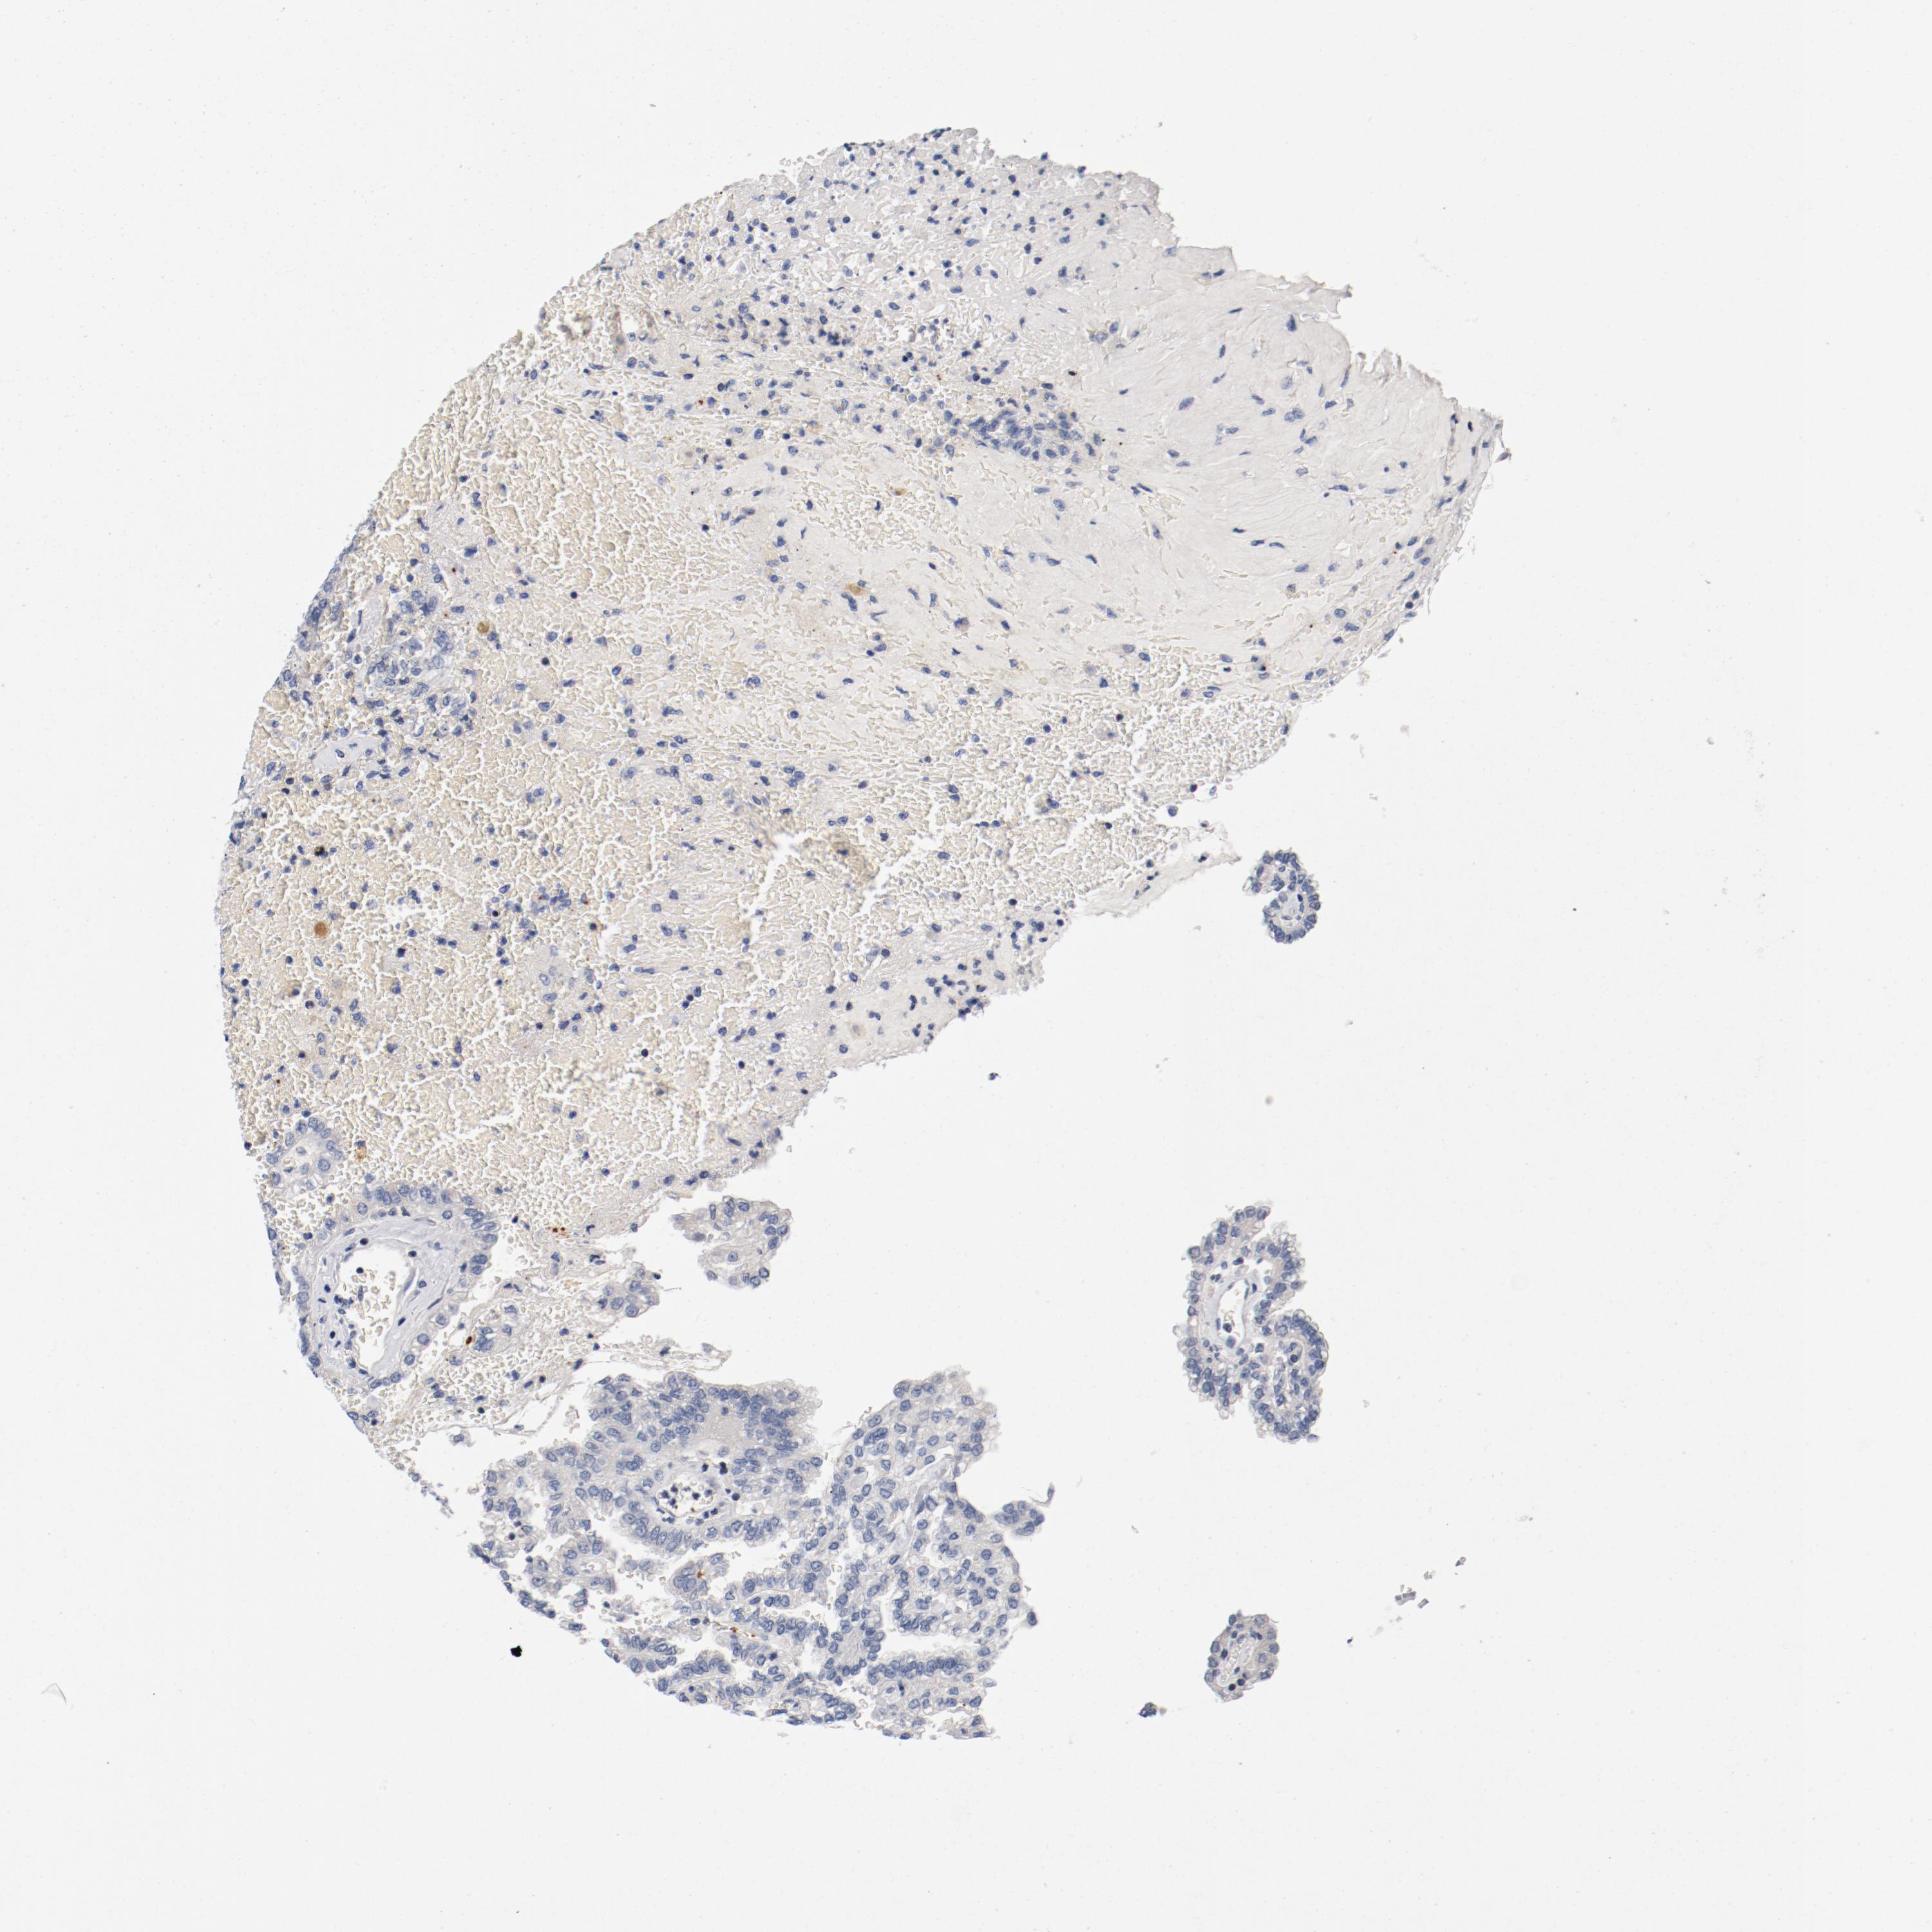

KIDNEY RENAL CLEAR CELL CARCINOMA (VALIDATION) - Interactive survival scatter ploti

The Survival Scatter plot shows the clinical status (i.e. dead or alive) for all individuals in the patient cohort, based on the same data that underlies the corresponding Kaplan-Meier plots. Patients that are alive at last time for follow-up are shown in blue and patients who have died during the study are shown in red.

The x-axis shows the expression levels (FPKM) of the investigated gene in the tumor tissue at the time of diagnosis. The y-axis shows the follow-up time after diagnosis (years). Both axes are complimented with kernel density curves demonstrating the data density over the axes. The top density plot shows the expression levels (FPKM) distribution among dead (red) and alive patients (blue). The right density plot shows the data density of the survived years of dead patients with high and low expression levels respectively, stratified using the cutoff indicated by the vertical dashed line through the Survival Scatter plot. This cutoff is automatically defined based on the FPKM cutoff that minimizes the p-score. The cutoff can be changed by dragging the vertical line or by entering a cutoff value in the square labeled "Current cut-off".

Under the Survival Scatter plot the p-score landscape (black curve; left axis) is shown together with dead median separation (red curve; right axis). Dead median separation is the difference in median mRNA expression between patients who have died with high and low expression, respectively. It is calculated as follows: median FPKM expression of dead patients with high expression - median FPKM expression of dead patients with low expression. This is intended to aid the user in visually exploring custom cutoffs and the associated p-scores and dead median separation.

Individual patient data is displayed and can be filtered by clicking on one or more of the category buttons on the top of the page. Categories describing expression level and patient information include: high, low, alive, dead, female, male and tumor stages. The scale of the x-axis can be toggled between linear and log-scale by clicking on the "x log" button. Mouse-over function shows TCGA ID, patient information and mRNA expression (FPKM) for each patient.

& Survival analysisi

Kaplan-Meier plots summarize results from analysis of correlation between mRNA expression level and patient survival. Patients were divided based on level of expression into one of the two groups "low" (under cut off) or "high" (over cut off). X-axis shows time for survival (years) and y-axis shows the probability of survival, where 1.0 corresponds to 100 percent.

PIM1 is not prognostic in Kidney Renal Clear Cell Carcinoma (validation)

Best expression cut offi

Based on the FPKM value of each gene, patients were classified into two groups and association between prognosis (survival) and gene expression (FPKM) was examined. The best expression cut-off refers the FPKM value that yields maximal difference with regard to survival between the two groups at the lowest log-rank P-value. Best expression cut-off was selected based on survival analysis .

When clicking on this number, the vertical dashed line indicating cut-off, the interactive survival plot, and the Kaplan-Meier curve will be adjusted to show results based on the best expression cut-off.

: 40.13

Average pTPM 32.4

Number of samples 100